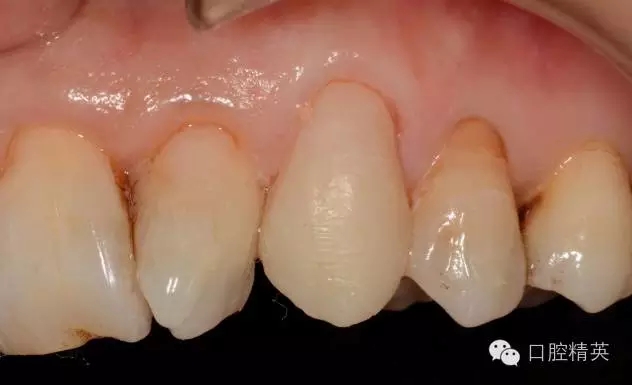

圖1 23口內(nèi)修復(fù)前情況:殘根位于齦上3MM,牙周無紅腫.